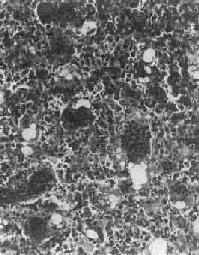

镜下,肿瘤主要由单核基质细胞及多核巨细胞等两种细胞组成(图17-6),间质血管丰富。基质细胞为梭形、卵圆形或圆形,细胞境界不清楚,常见胞浆突起。细胞核较大,染色质量中等,可具有一个核仁。多核巨细胞常较均匀地散布在基质细胞之间,是为本瘤的特点。多核巨细胞的直径常为30~60μm,核数一般为15~20个,最多可达100个以上,常聚集在细胞的中央。核的形态与单核基质细胞相似。细胞边界不规则,但分界较清楚,胞浆丰富,略呈嗜碱性,有时还可见含大量脂类的泡沫细胞。本瘤间质血管丰富,有多少不等的胶原纤维。肿瘤本身无成骨现象,但有时见有类骨组织及新生骨小梁,常见于纤维组织的周围,可能是一种反应性新骨形成或病理性骨折后形成的骨痂。

图17-6 骨巨细胞瘤(Ⅰ级)

肿瘤由大量基质细胞和多核巨细胞两种细胞组成